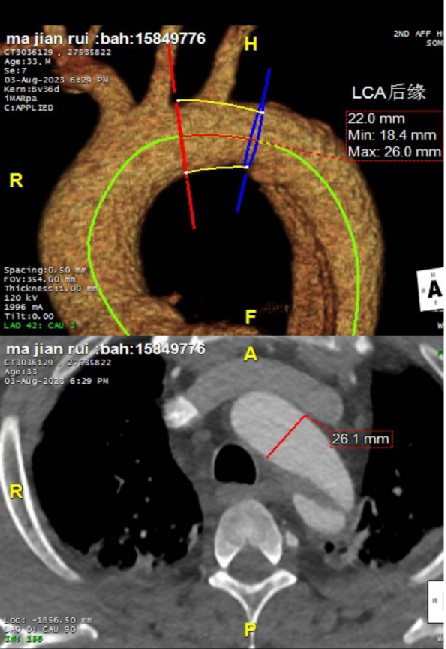

患者很年轻,不希望支架开窗或干扰左锁骨下动脉,但破口紧邻左锁骨下动脉小弯侧(小弯侧破口距锁骨下动脉只有7mm,大弯侧9mm),挑战比较大。需要评估是否延长近端锚定区以覆盖病变,同时避免影响重要分支血供。

③ 支架选择策略:通过术前规划模拟不同口径、长度支架的植入效果,预测术后真腔重塑及对血流动力学(如压力梯度、远端供血)的影响,最终选择适配血管直径及病变范围的支架。

根据体外模拟演示和临床可选择支架情况,判定28mm支架对真腔重塑,远端血流动力学恢复效果最佳,决定植入直径28mm,长度160mm胸主动脉支架